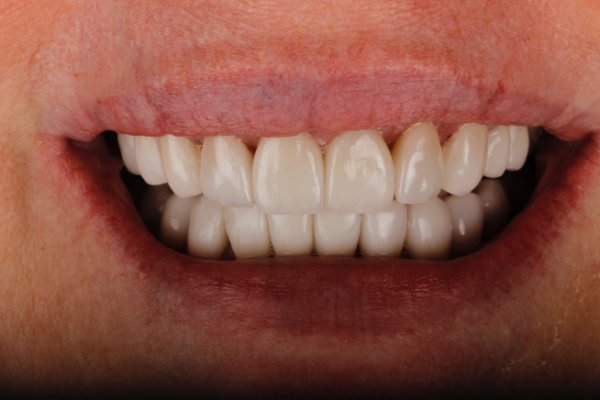

In the case shown, (Figure 1a) the patient wanted her teeth to be completed prior to her wedding in 14 weeks from the time she presented. She also requested a material with the longest performing clinical lifespan.

If all of these considerations are taken into account with this case, we can see that the upper right central incisor would be subject to significant tooth reduction (Figures 1b and 1c) and the risk of iatrogenic pulpal death would be increased. Even with immediate dentine sealing and other protective practices adopted.

So, prior to a hygiene work up, the patient was then assessed from an orthodontic perspective for short-term pre-restorative orthodontics. This was to improve tooth position (Figures 2 a,b and c) and allow for a less destructive tooth preparation.